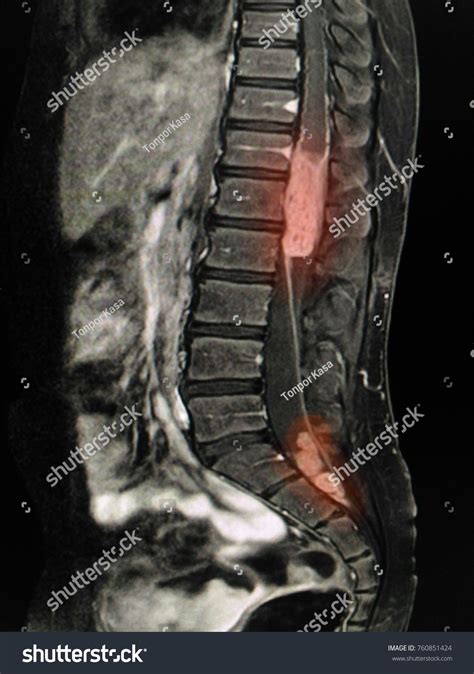

A cancer tumor back diagnosis generally refers to an abnormal growth of cells located within the spinal canal or the bones of the spine (vertebrae). These tumors are classified based on their location: intradural-extramedullary (inside the spinal canal but outside the spinal cord), intramedullary (inside the spinal cord), or extradural (outside the spinal cord, often involving the bone).

MRI Scan The gold standard for visualizing soft tissues and nerve compression.